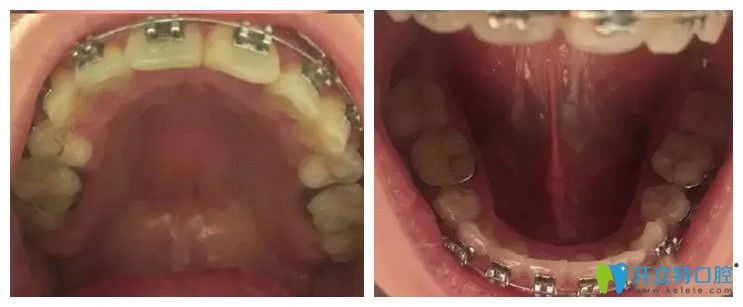

我印象比較深刻的是,剛開始戴金屬牙套,那真是有點(diǎn)不適應(yīng),口粘膜都快磨破了,另外,就是復(fù)診時(shí)候那種酸脹的感覺,不過,等自己適應(yīng)了也就沒事了,并且自己還得堅(jiān)持啊。過程的中照片我就不曬了,來張快摘牙套的照片吧!

<戴金屬牙套即將畢業(yè)的口內(nèi)照片>:↓↓

戴金屬牙套即將畢業(yè)的口內(nèi)照片